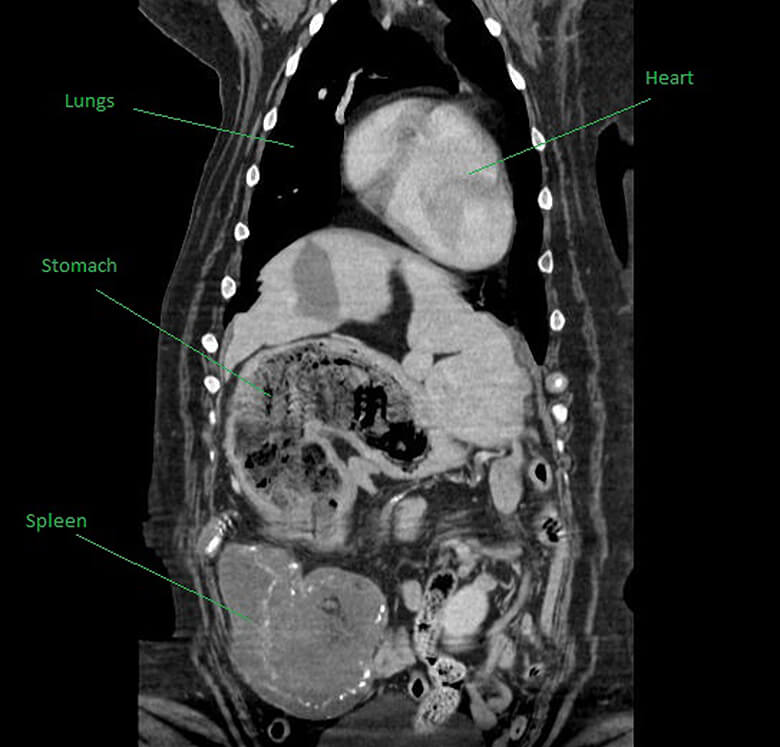

When Jane Dickinson took her beloved dog Maisy to the vet, she was fearing for the worst. Her St. Bernard was going into surgery to remove a mass found on the spleen, along with examining her unusually full stomach that wasn’t digesting any food. The vet thought it may be cancer – and wondered if Maisy would even make it through the operation.

But when Dr. Nick Blackburn went in to remove the spleen, he discovered what was really going on with Maisy. The 8-year-old dog didn’t have cancer; she had a case of the teddy bears. According to Dickinson, Maisy had apparently devoured FOUR of her Chihuahua’s stuffed toys.